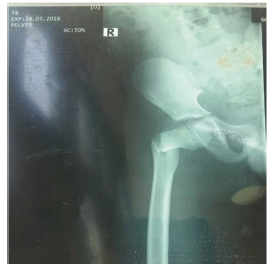

All the children had operative management either by open reduction and internal fixation (ORIF), or closed reduction and internal fixation (CRIF) under fluoroscopy since all 4 patients had displaced fractures. After patient were followed up for at least 2 years, all 4 were found to be asymptomatic clinically with no pain, no limp shortening and had no radiological evidence of AVN. Hence using the Ratliff ’s criteria, all 4 patients had good outcomes (100%) as shown in Table 2, despite 1 patient having complication of primary screw cut out on postoperative day 10 with subsequent radiograph showing implant failure (Figure 1).

Figure 1:X-ray showing failed percutaneous pinning with two cannulated screws post op.

This occurred in the 8-year-old boy who had his falling school wall landing on the right thigh whilst playing at school (Figure 2). He had closed reduction and percutaneous pinning with 2 cannulated screws without hip spica. Child was doing well post operatively on the ward until day 10 when he suddenly sat upright in a chair to receive lessons from the school teacher. He was in sudden excruciating pain and subsequent repeated radiograph confirmed the cut out of the cannulated screws (Figure 1). He later had closed reduction and percutaneous pinning with 22mm-Kirschner wire and No. 5 TiCron tension band as well as hip spica applied after previous screws removed (Figure 3 & 4).